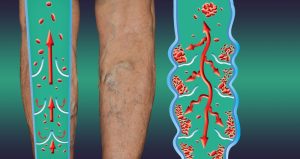

Σύμφωνα με την American Cancer Society, ορισμένα πρόσθετα συμπτώματα περιλαμβάνουν δυσπεψία, ναυτία, διαβήτη, φαγούρα, πυρετό ακόμα και ρίγη. Ένα ιδιαίτερα ανησυχητικό σύμπτωμα; Θρόμβωση.

Στην πραγματικότητα, ο καρκίνος του παγκρέατος είναι ένας από τους καρκίνους που πιθανότερα προκαλούν θρόμβους, με έως και το 36% των ασθενών να βιώνουν επιπλοκές από πήξη.

«Μερικές φορές, το πρώτο στοίχειο ότι κάποιος έχει καρκίνο του παγκρέατος είναι ένας θρόμβος αίματος σε μια μεγάλη φλέβα, συχνά στο πόδι», εξηγεί ο οργανισμός.

«Αυτό ονομάζεται βαθιά φλεβική θρόμβωση ή DVT. Τα συμπτώματα μπορεί να περιλαμβάνουν πόνο, οίδημα, ερυθρότητα και αίσθηση ζέστης στο πληγέν πόδι. Μερικές φορές ένα κομμάτι του θρόμβου μπορεί να σπάσει και να ταξιδέψει στους πνεύμονες, κάτι που μπορεί να προκαλέσει δυσκολία στην αναπνοή ή πόνο στο στήθος. Ένας θρόμβος αίματος στους πνεύμονες ονομάζεται πνευμονική εμβολή ή PE.»

Παρόλο που ο καρκίνος του παγκρέατος είναι μια πιθανή αιτία, οι θρόμβοι αίματος μποούν από μόνοι τους να είναι θανατηφόροι. Εάν παρατηρήσετε πόνο, ερυθρότητα, οίδημα ή αίσθηση ζέστης γύρω από έναν θρόμβο, ή βιώσετε δύσπνοια, πόνο στο στήθος ή πόνο στην πάνω πλάτη, ο Οργανισμός Cancer Research UK προειδοποιεί ότι πρέπει να «επικοινωνήσετε αμέσως με τον ιατρό σας».